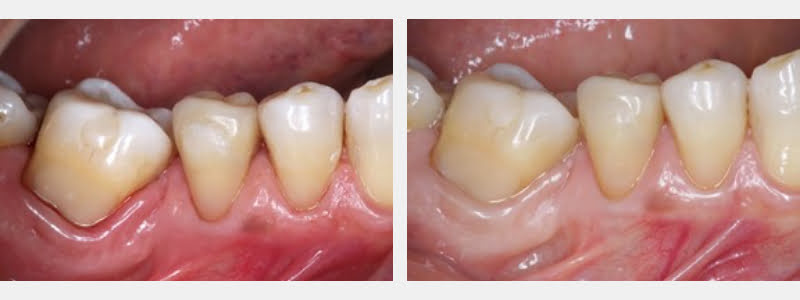

In the following steps, a modified 212 clamp was used to treat a partially edentulous 67-year-old patient, who presented evident signs of parafunction and needed cervical restorations.

- Cervical carious and NCCL were identified on teeth #31, #29, and #28.

- Performed finishing and polishing of the restoration using polishing discs.